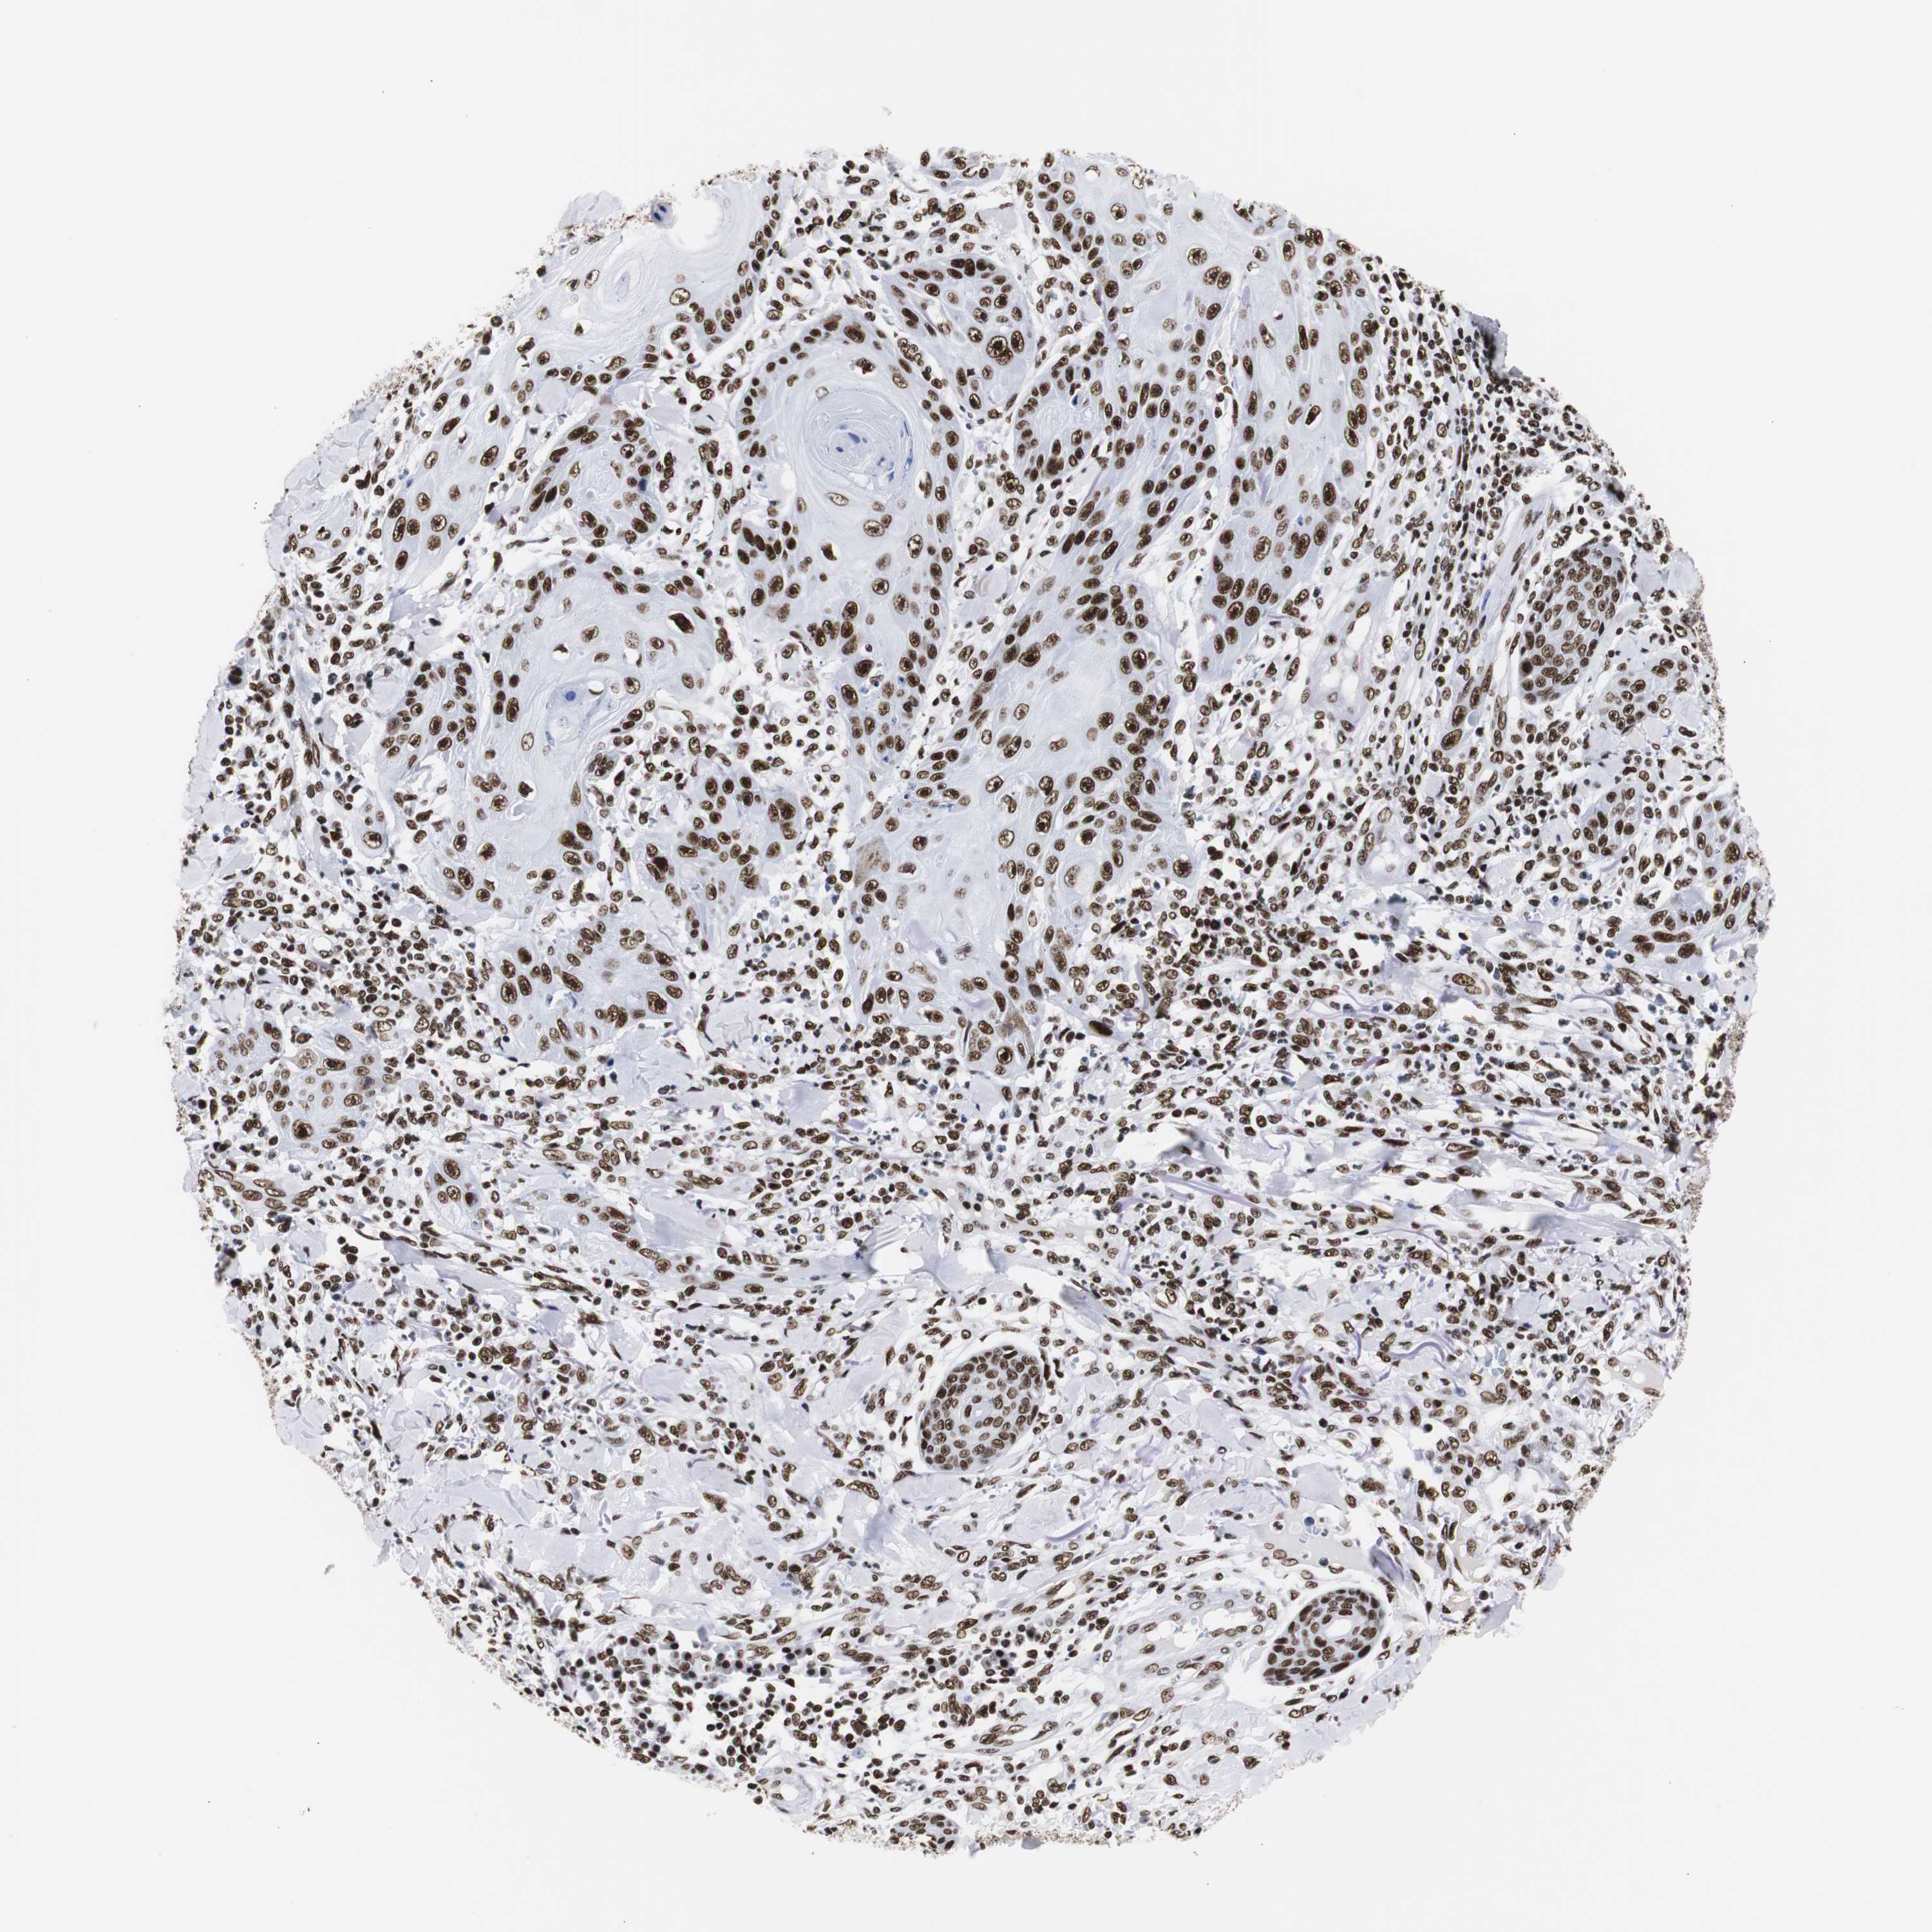

SKIN CANCER - Protein expressioni

A mouse-over function shows sample information and annotation data. Click on an image to view it in a full screen mode. Samples can be filtered based on level of antibody staining by selecting one or several of the following categories: high, medium, low and not detected. The assay and annotation is described here.

Each image is clickable and will lead to virtual microscopy that enables deeper exploration of all samples and also displays staining intensity scores, fraction scores and subcellular localization as well as patient and tissue information for each sample.

Antibody CAB004436

Staining

High

Strong

>75%

Location

Nuclear

Basal cell carcinoma